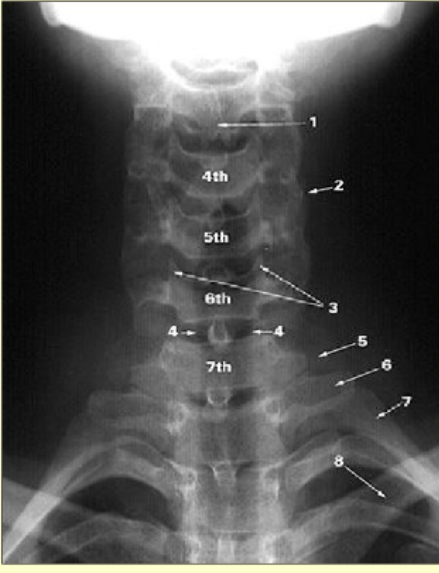

Label this image

bifid spinous process of C3

superimposed articular processes

uncinate process

trachea

transverse process of C7

transverse process of T1

1st rib

clavicle